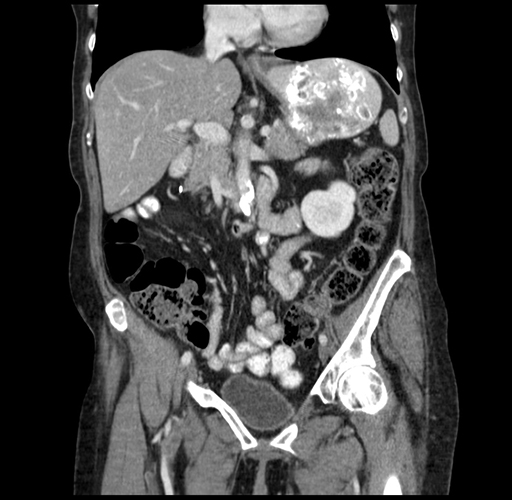

Pre-Chemo: Coronal Venous

Coronal Venous